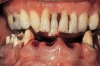

Figure 13  Preoperative intraoral facial view.

Figure 13